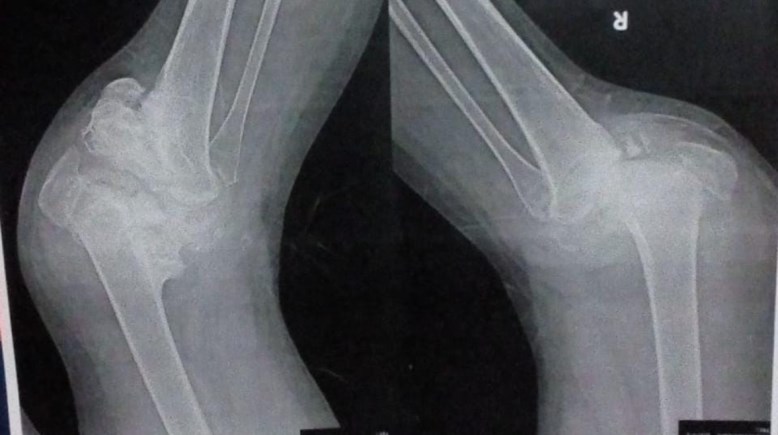

بين شبح البتر وأمل السفر.. "دعاء" فتاة يفتت "شاركوت" عظامها (خاص)